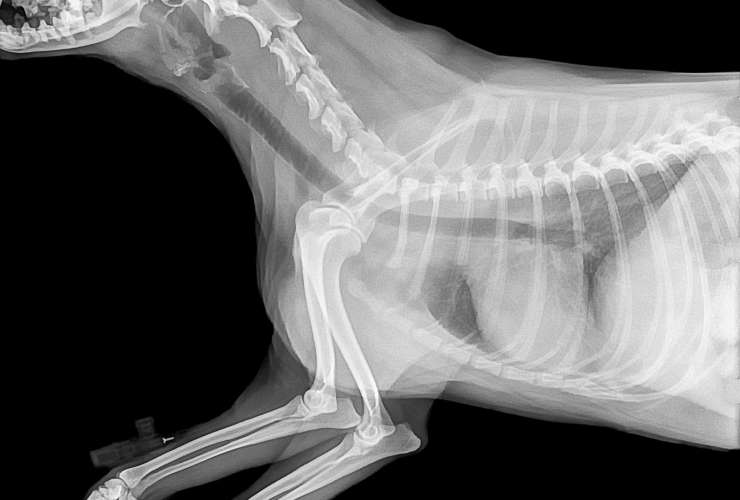

El estudio radiográfico simple es una herramienta clave en la medicina veterinaria que utiliza rayos X para obtener imágenes detalladas del interior de tu mascota. Esta técnica permite a nuestros veterinarios ver claramente los huesos y órganos internos, facilitando la detección y el diagnóstico de una variedad de condiciones de salud.

- Evaluación de fracturas óseas: Identificación de fracturas y lesiones en los huesos.

- Diagnóstico de enfermedades pulmonares: Detección de afecciones respiratorias como infecciones o tumores

- Inspección de problemas abdominales: Detección de cuerpos extraños, tumores o problemas en órganos internos.